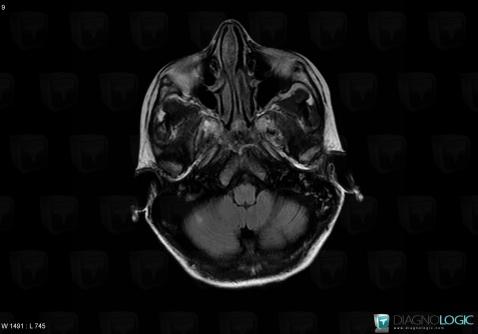

Toxoplasmosis, Basal ganglia and capsule, MRI

Here is the specific information in the key image above:

- Diagnosis Toxoplasmosis (link to Abscess), Location(s) Basal ganglia and capsule, with gamuts Basal ganglia T2W or FLAIR hyperintense lesion